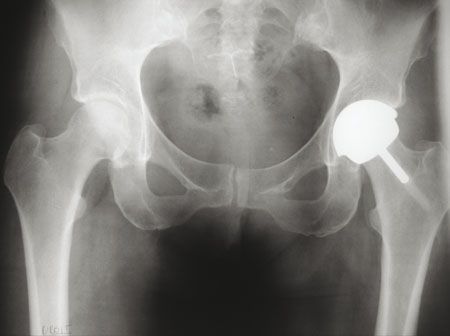

Mise au point Le resurfaçage total de la hanche : retour du passé ou arthroplastie moderne ? , Philippe Chiron Hôpital Pierre-Paul Riquet, Toulouse, France N°174 - Mai 2008 ● 13 min de lecture